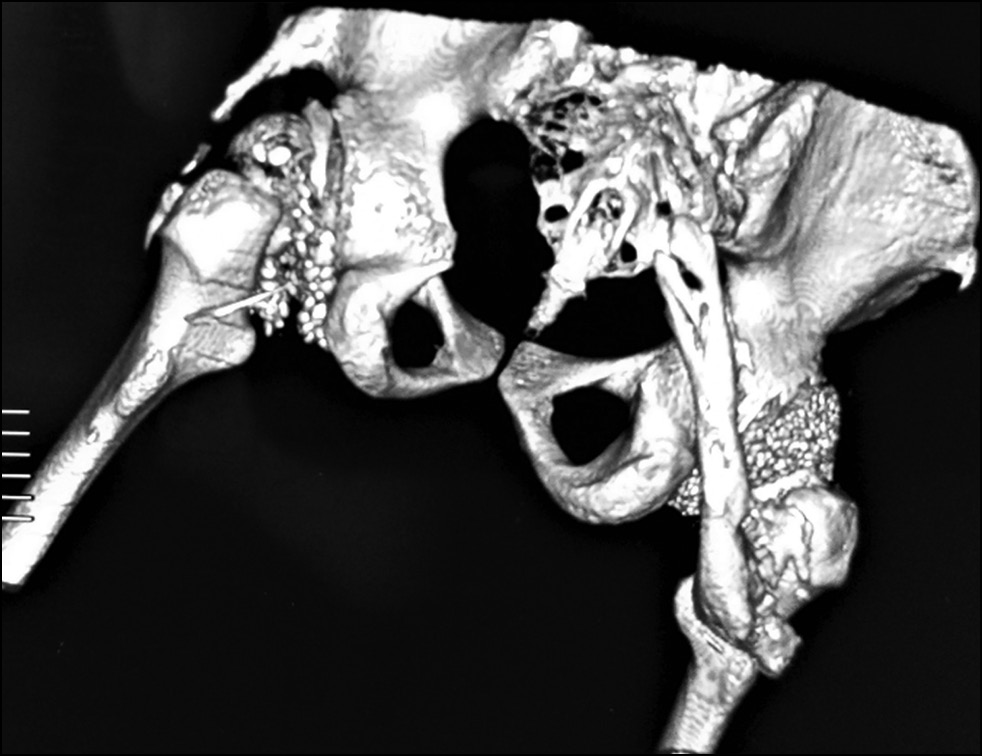

Control radiographs revealed multiple heterotopic ossifications of the axial and peripheral skeleton and submandibular region and multiplanar spinal deformity (Figs. 1–3). Computed tomography revealed synostosis of the 2nd–5th cervical vertebrae, which exhibited fusion of not only their posterior elements but also their bodies (Figs. 4 and 5). Synovial chondromatosis, one of the most common manifestations of FOP, was identified during a hip joint examination (Fig. 6). In addition to intra-articular chondromal bodies, heterotopic ossifications in the hip joints completely inhibit the movements in this skeletal region and significantly impeded walking (Figs. 7 and 8).

Fig. 7. Three-dimensional CT reconstruction of the hip joints, anterior view: marked synovial chondromatosis.